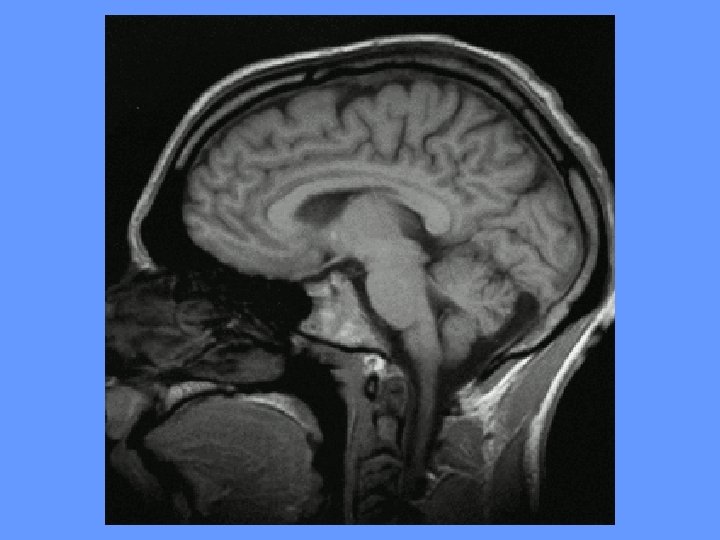

Lipohyalinose